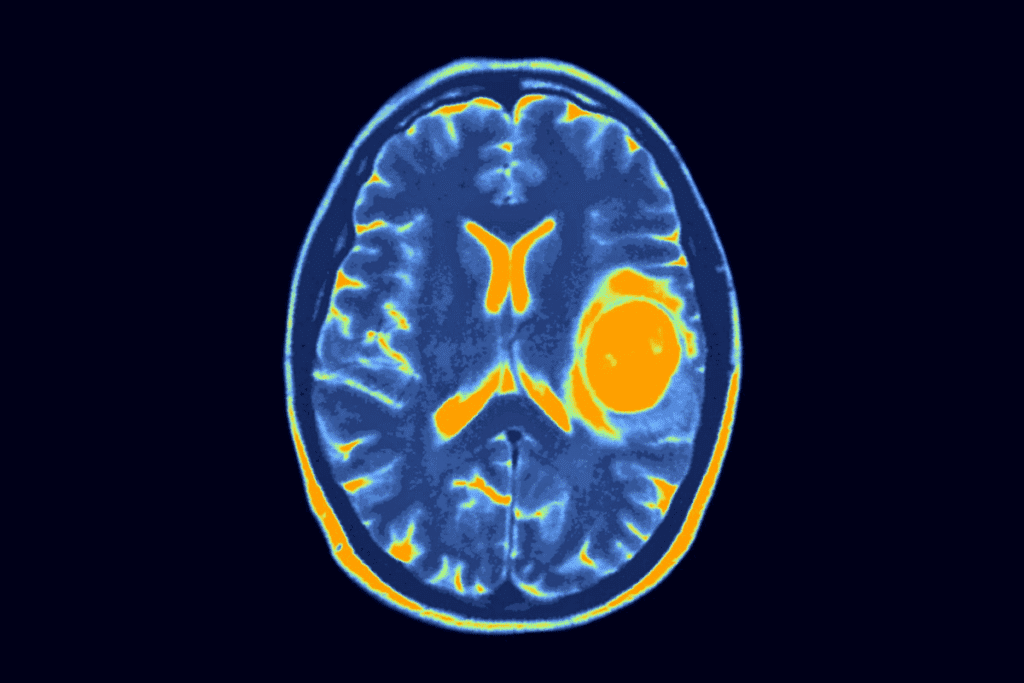

Diagnostic Challenges in Asymptomatic Cases

Asymptomatic brain tumors in children are hard to diagnose. They don’t show symptoms, making it tough for doctors to find them. This is because there are no clear signs to look for.

Current Limitations in Screening and Detection

Screening for brain tumors has its limits, mainly in cases without symptoms. MRI and CT scans are very good at finding tumors. But, they’re not used for regular checks because of the cost, availability, and worries about radiation.

We usually wait for symptoms to appear before testing further. But, for silent brain tumors, this can cause a delay in finding out what’s wrong.

When Tumors Are Found Incidentally

At times, doctors find brain tumors by accident during tests for other reasons. This shows how tricky it is to spot these tumors. It also points out the importance of keeping a close eye on things.

| Diagnostic Method | Advantages | Limitations |

| MRI | High-resolution images, no radiation | Costly, not always readily available |

| CT Scan | Quick, widely available | Radiation exposure, less detailed soft tissue images |

It’s key to understand these challenges to get better at finding tumors early. By knowing what we can do better and using new tech, we can spot these tumors sooner in kids.

Diagnostic Procedures for Detecting Silent Brain Tumors

Finding brain tumors in kids without symptoms is tough. New medical tech has helped us spot these tumors early. This is even when they don’t show any symptoms.

Imaging Technologies and Their Effectiveness

Imaging tech is key in finding silent brain tumors. Magnetic Resonance Imaging (MRI) stands out. It gives clear brain images, helping doctors find tumors early.

It’s a vital tool in finding tumors without symptoms.

Computed Tomography (CT) scans also help find brain tumors. They’re fast and easy to get, but they use radiation. They might not show soft tissue details as well as MRI.